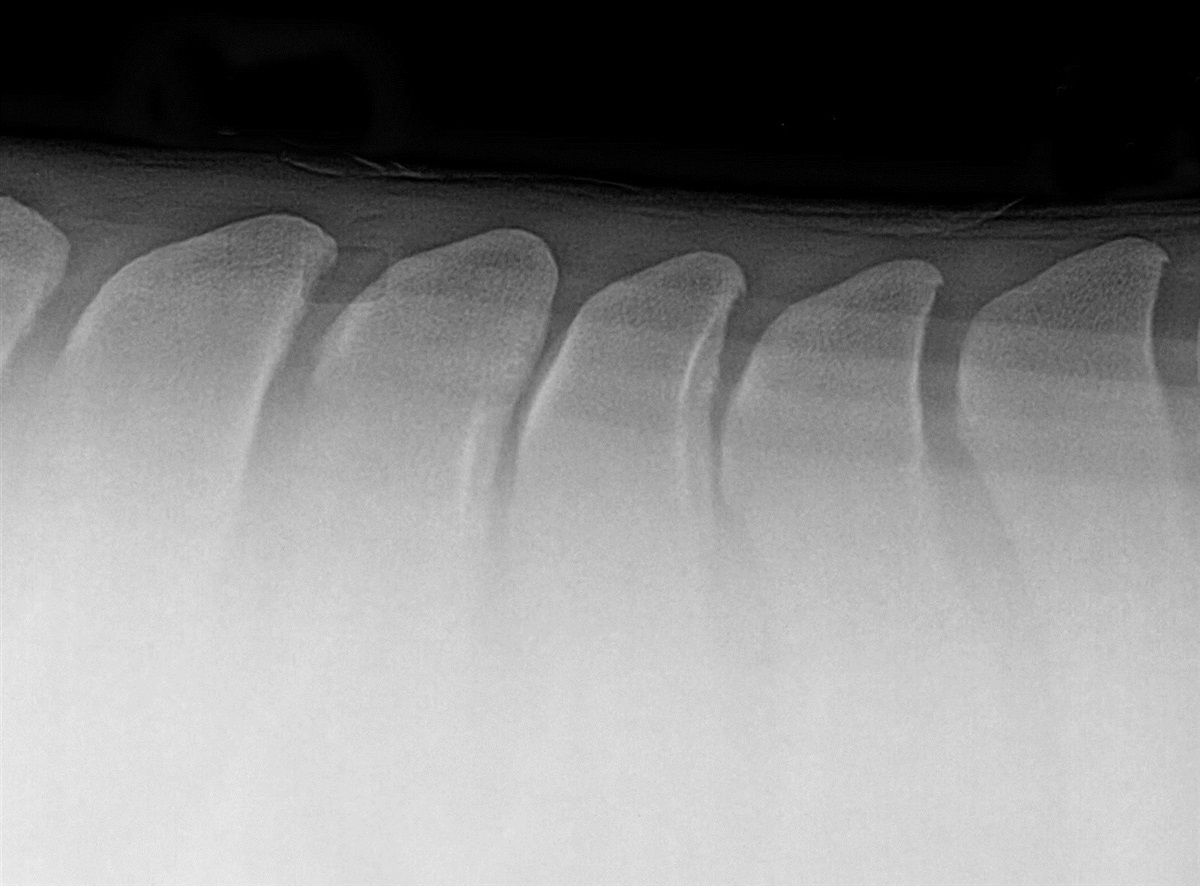

Tætsiddende torntappe er ikke (alene) en røntgendiagnose

Af faglige artikler kan du blandt andet læse om det nyeste indenfor tætsiddende torntappe eller populært kaldet "kissing spine". I godt 40 år har diagnosen kostet avlere millioner af kroner, heste er erklæret uegnede til ridebrug, og forsikringsselskaberne tager deres forbehold – men vi er siden blevet klogere.

I forbindelse med SEGES Hestekongres i januar holdt dyrlæge og ph.d. Nicolai Jarløv fra Hørsholm Hestepraksis et særdeles interessant foredrag, hvor han fortalte om, at hvad, der startede som en røntgendiagnose, har vist sig at være meget mere komplekst.

I dag er erfaringerne med diagnosticeringen af kissing spine/tætsiddende torntappe langt større, og der er en udbredt erkendelse af, at røntgen ikke giver den endegyldige sandhed om denne lidelse. Bliv klogere på hvorfor i marts-udgivelsen af Ridehesten.